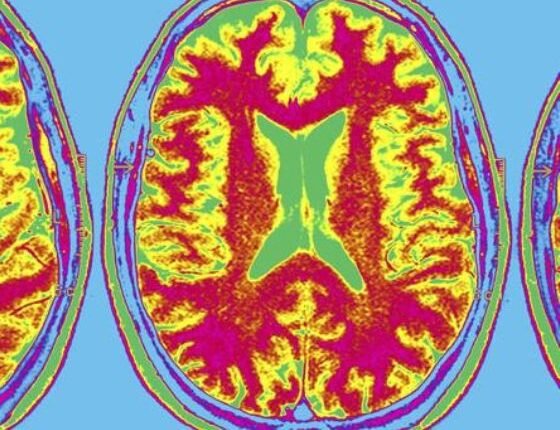

Για την μελέτη ο Bryan και οι συνεργάτες του χρησιμοποίησαν μαγνητική τομογραφία για να εξετάσουν τους εγκεφάλους 614 ατόμων με διαβήτη τύπου 2. Οι εθελοντές είχαν διαβήτη κατά μέσο όρο περίπου 10 χρόνια.